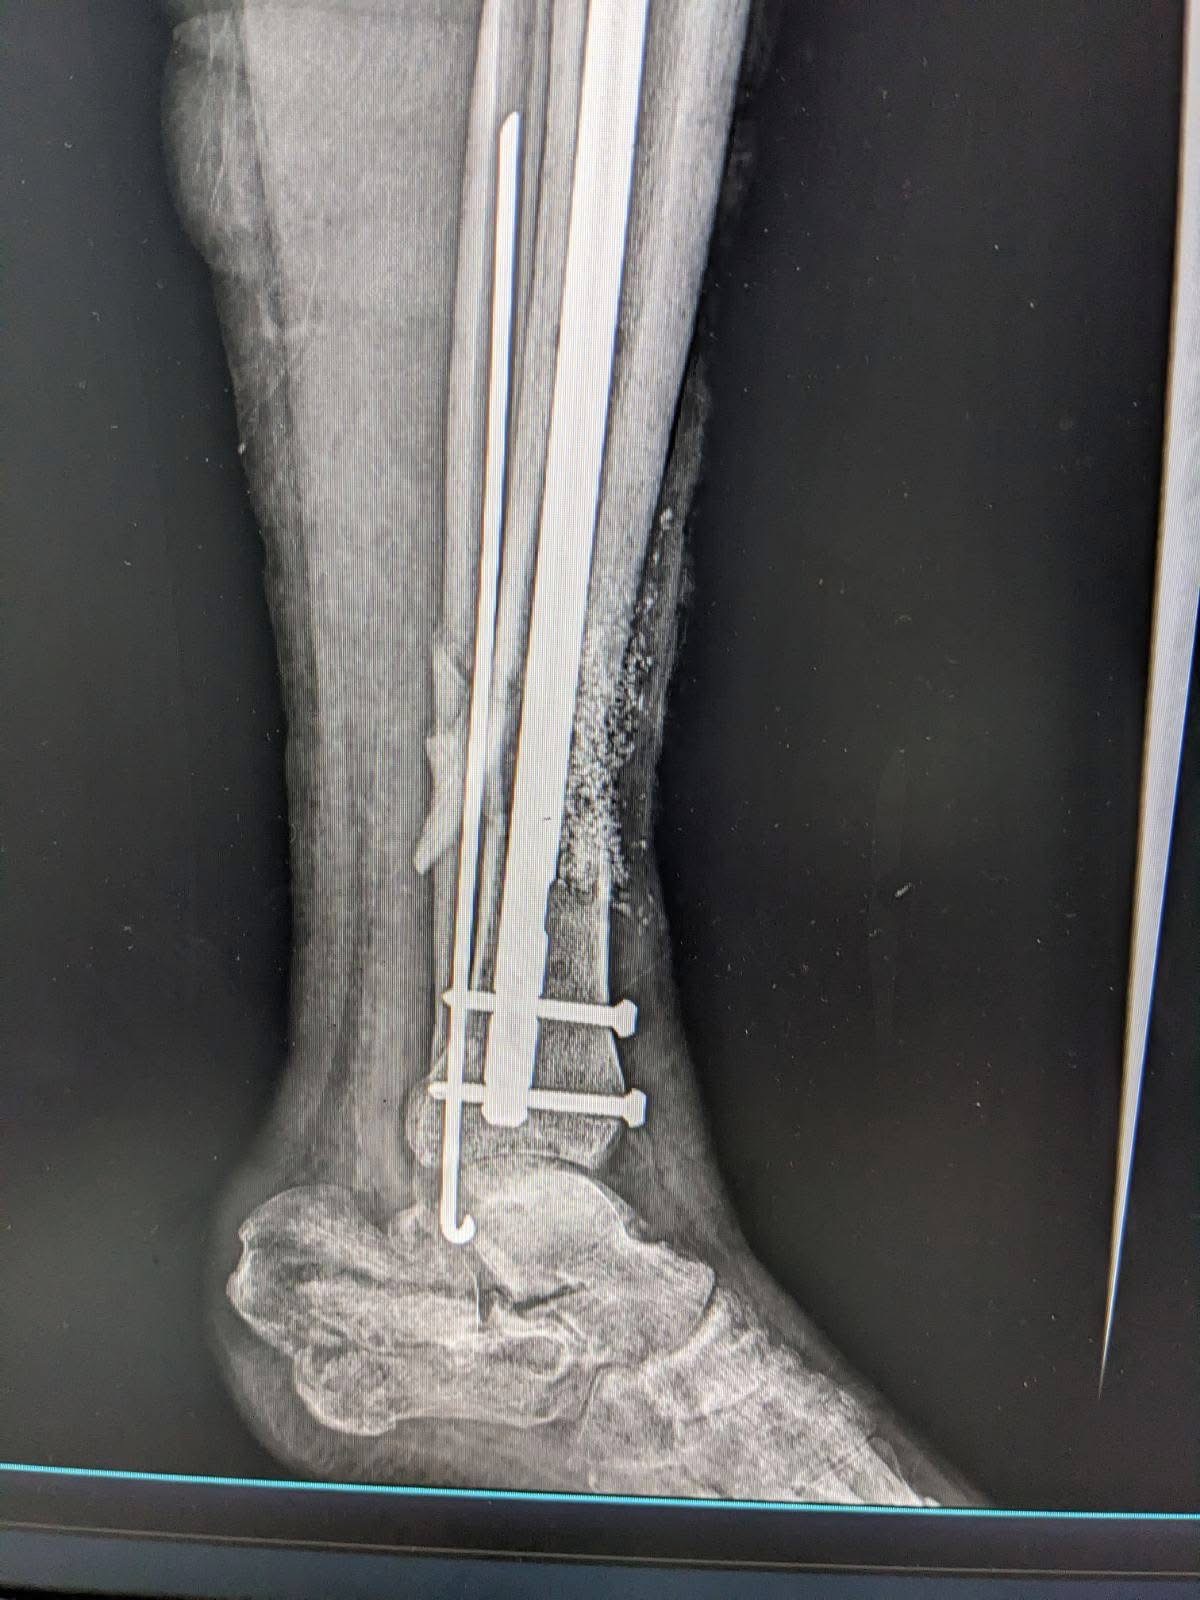

У Богородчанській центральній лікарні виконали складне реконструктивне оперативне втручання військовослужбовцю з післятравматичним дефектом кісткової тканини.

Як повідомили у медзакладі, під час операції лікарі відновили цілісність кістки із застосуванням аутокісткової пластики (власної кістки пацієнта) у поєднанні з біоактивним біосклом. Такий сучасний підхід дозволяє стимулювати регенерацію кісткової тканини, покращити остеоінтеграцію, зменшити ризик ускладнень та сприяти швидшому функціональному відновленню.

Втручання провела команда травматологів-ортопедів із дотриманням сучасних принципів реконструктивної хірургії.